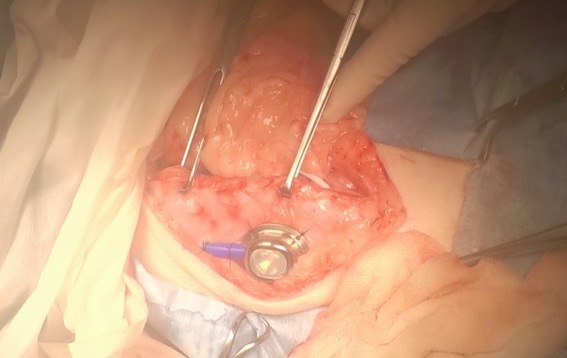

皮下に埋め込むスワールポートです。↓↓

両側に設置した症例です。↓↓